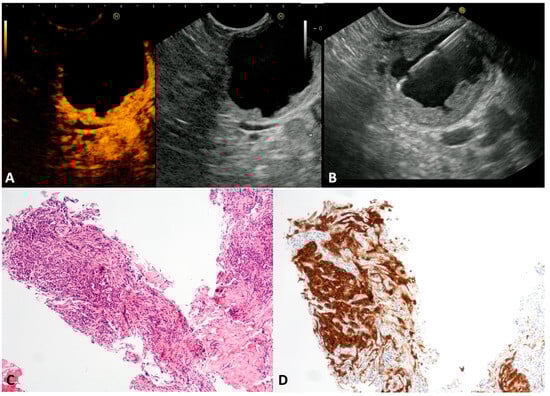

The published literature has reported that cNETs account for 13% of all pancreatic NETs []. Despite small cystic spaces in the context of a solid tumor being common in pancreatic NET, often assuming a “bull-eye” appearance with a central cyst and thickened wall, the complete cystic appearance is rare, and tendentially more indolent. cNETs may be sporadic or associated with multiple neuroendocrine neoplasia (MEN), or the von Hippel–Lindau or Wermer syndromes []. In our series, seven asymptomatic patients (four males, mean age 53 ± 6.8 years) presented a unilocular cyst (mean size 25.8 ± 6.7 mm) with a thickened wall (Figure 2A) located in the head, in the body, and in the tail of the pancreas in one, two and four cases, respectively. At CH-EUS, the hyperenhancement of thickened walls was observed (Figure 2B). The TTNB gathered histological specimens suitable for immunohistochemical stains in all cases. Numerous small round cells (Figure 2C) positive to chromogranin A and synaptophysin stains (Figure 2D) confirmed the neuroendocrine nature of the cysts. The evaluation of the proliferative index (Ki-67) of the TTNB specimens was possible in 6/7 (85.7%). All tumors were G1. Four out of seven patients underwent surgical resection that confirmed the preoperative diagnosis and the tumor grading. The remaining patients continued to be observed, with no changes over the follow-up period.

Figure 2.

Cystic neuroendocrine neoplasm. Contrast-harmonic endoscopic ultrasound showing hyper-enhanced walls of an unilocular cyst (A). Endoscopic ultrasound-guided through-the-needle biopsy targeting the thickened walls (B). The cyst wall is almost completely composed of small, tightly packed epithelial cells (C) that stain intensely for the neuroendocrine marker Synaptophysin (D). Hematoxylin–eosin original magnification ×100 (C). Synaptophysin original magnification ×100 (D).